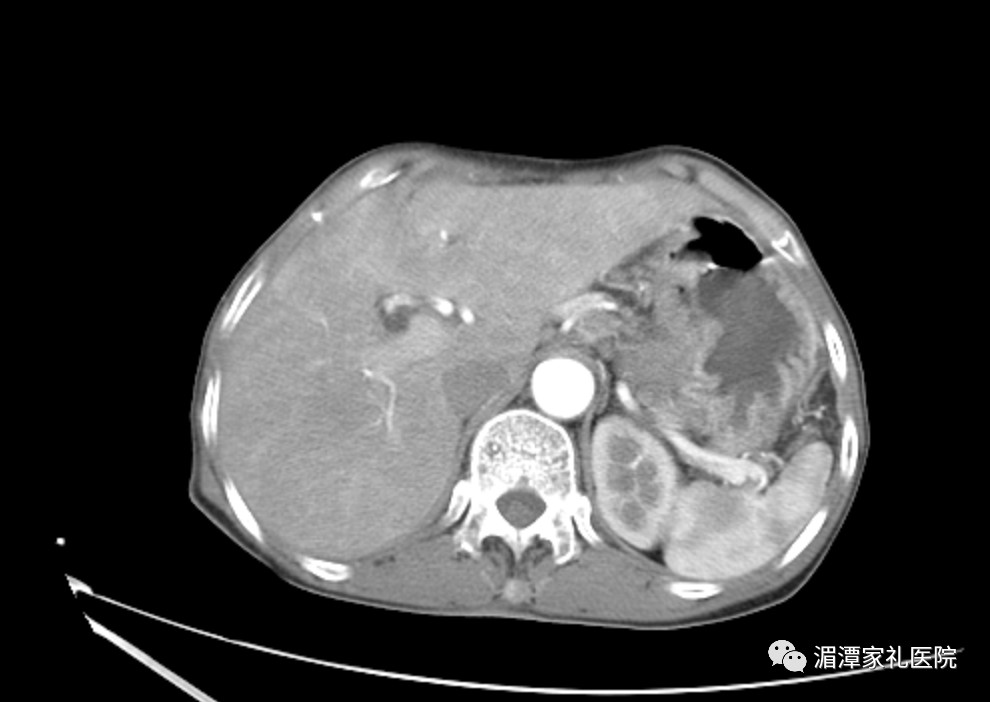

术前影像

胸心外科主任医师赵正源率领团队进一步检查之后发现,唐婆婆体内肿瘤比较大,肿瘤距离胃左动脉仅有很小的间隙,手术中分离胃左动脉时如果稍有不慎便会造成大出血。但是如果不及时将肿瘤切除,随着病情加重,唐婆婆将再也无法吞咽食物。在充分完善了术前准备及术前检查后,凭借丰富的手术经验,赵正源率领团队于11月10日为唐婆婆顺利实施了手术,成功切除了巨大肿瘤。